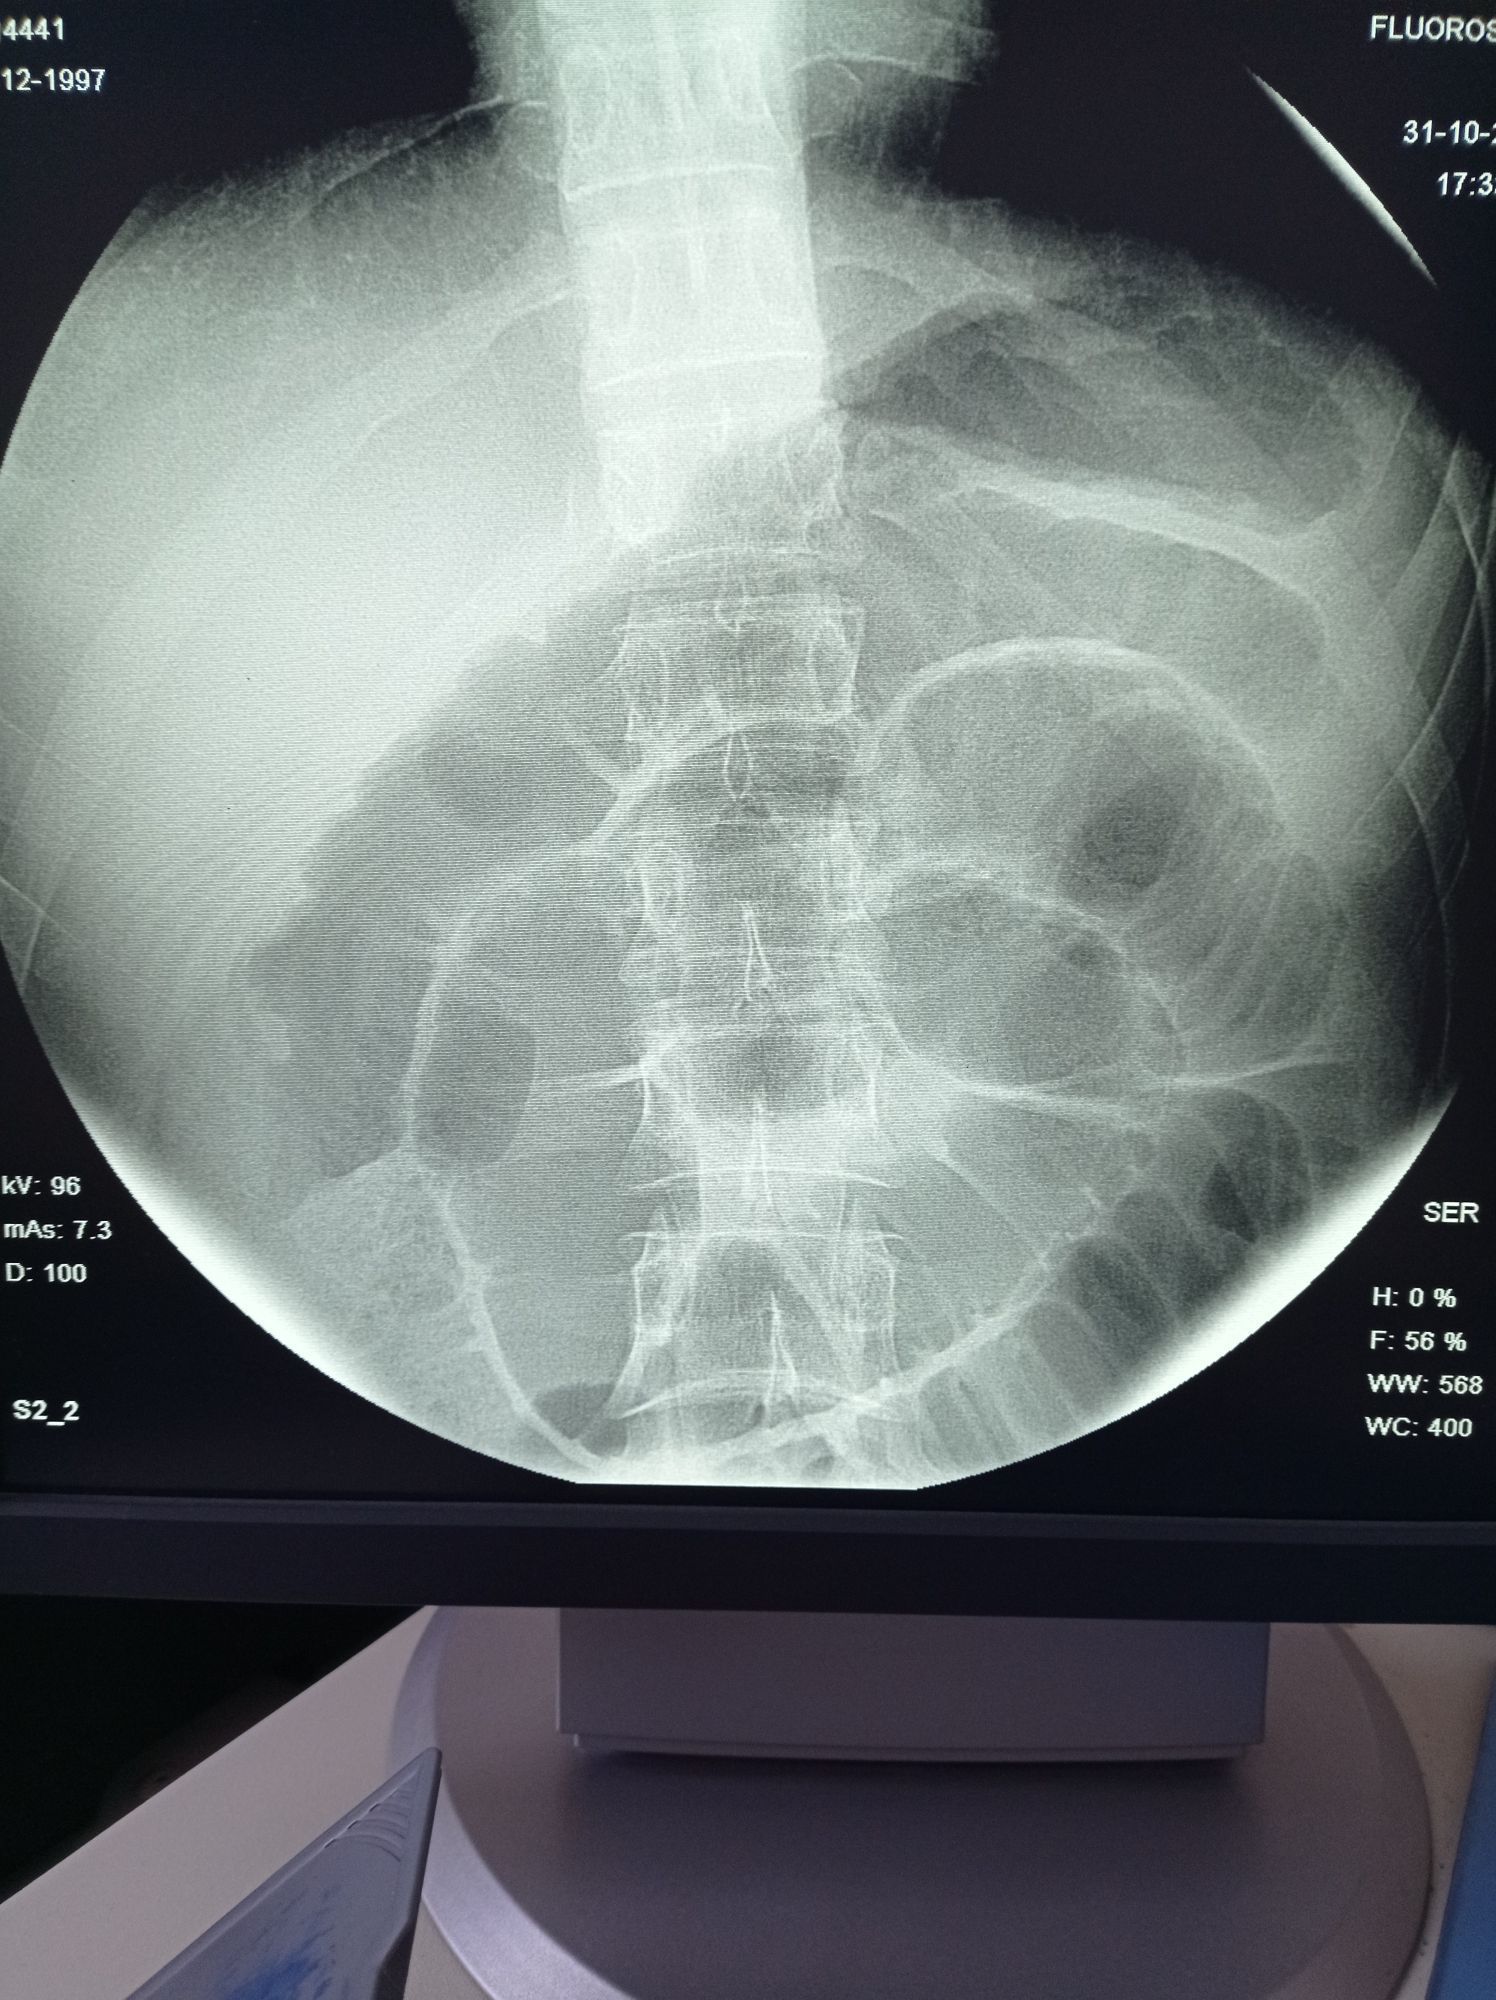

Acute bowel obstruction

Surgery

Bowelobstruction

Acute Pain